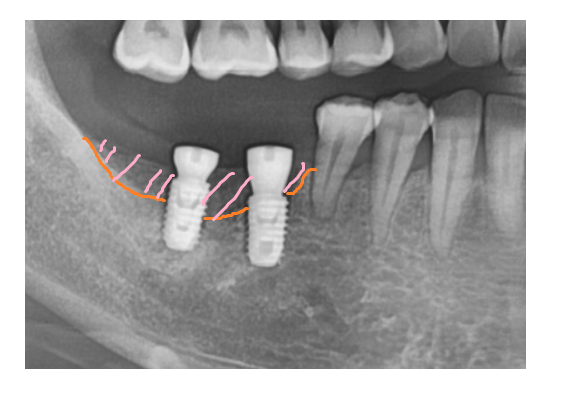

위의 사진속 뼈 음영 색깔이 다른게 느껴지시나요?

231213

임플란트는 심었지만

주황색 선 위쪽으로는 뼈가 충분하지 않아요~

뼈가 충분한 아래쪽은 밀도가 높아 좀 더 하얀색이죠~?